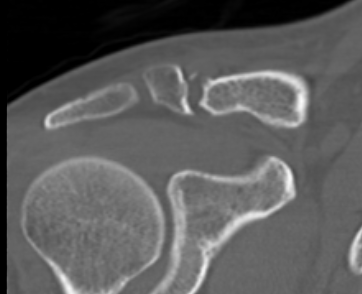

Fracture lateral to the CC ligaments Non displaced

Fracture medial to the CC ligaments CCL ligaments attached to lateral fragment Medial fragment displaced superiorly |

Between conoid and trapezoid Conoid disrupted Trapezoid remains attached to the lateral fragment |

Lateral to CC ligaments Intra-articular extension Stable |

Periosteal sleeve disruption Pediatric Medial fragment displaced |

Comminuted Type II Medial fragment displaced |